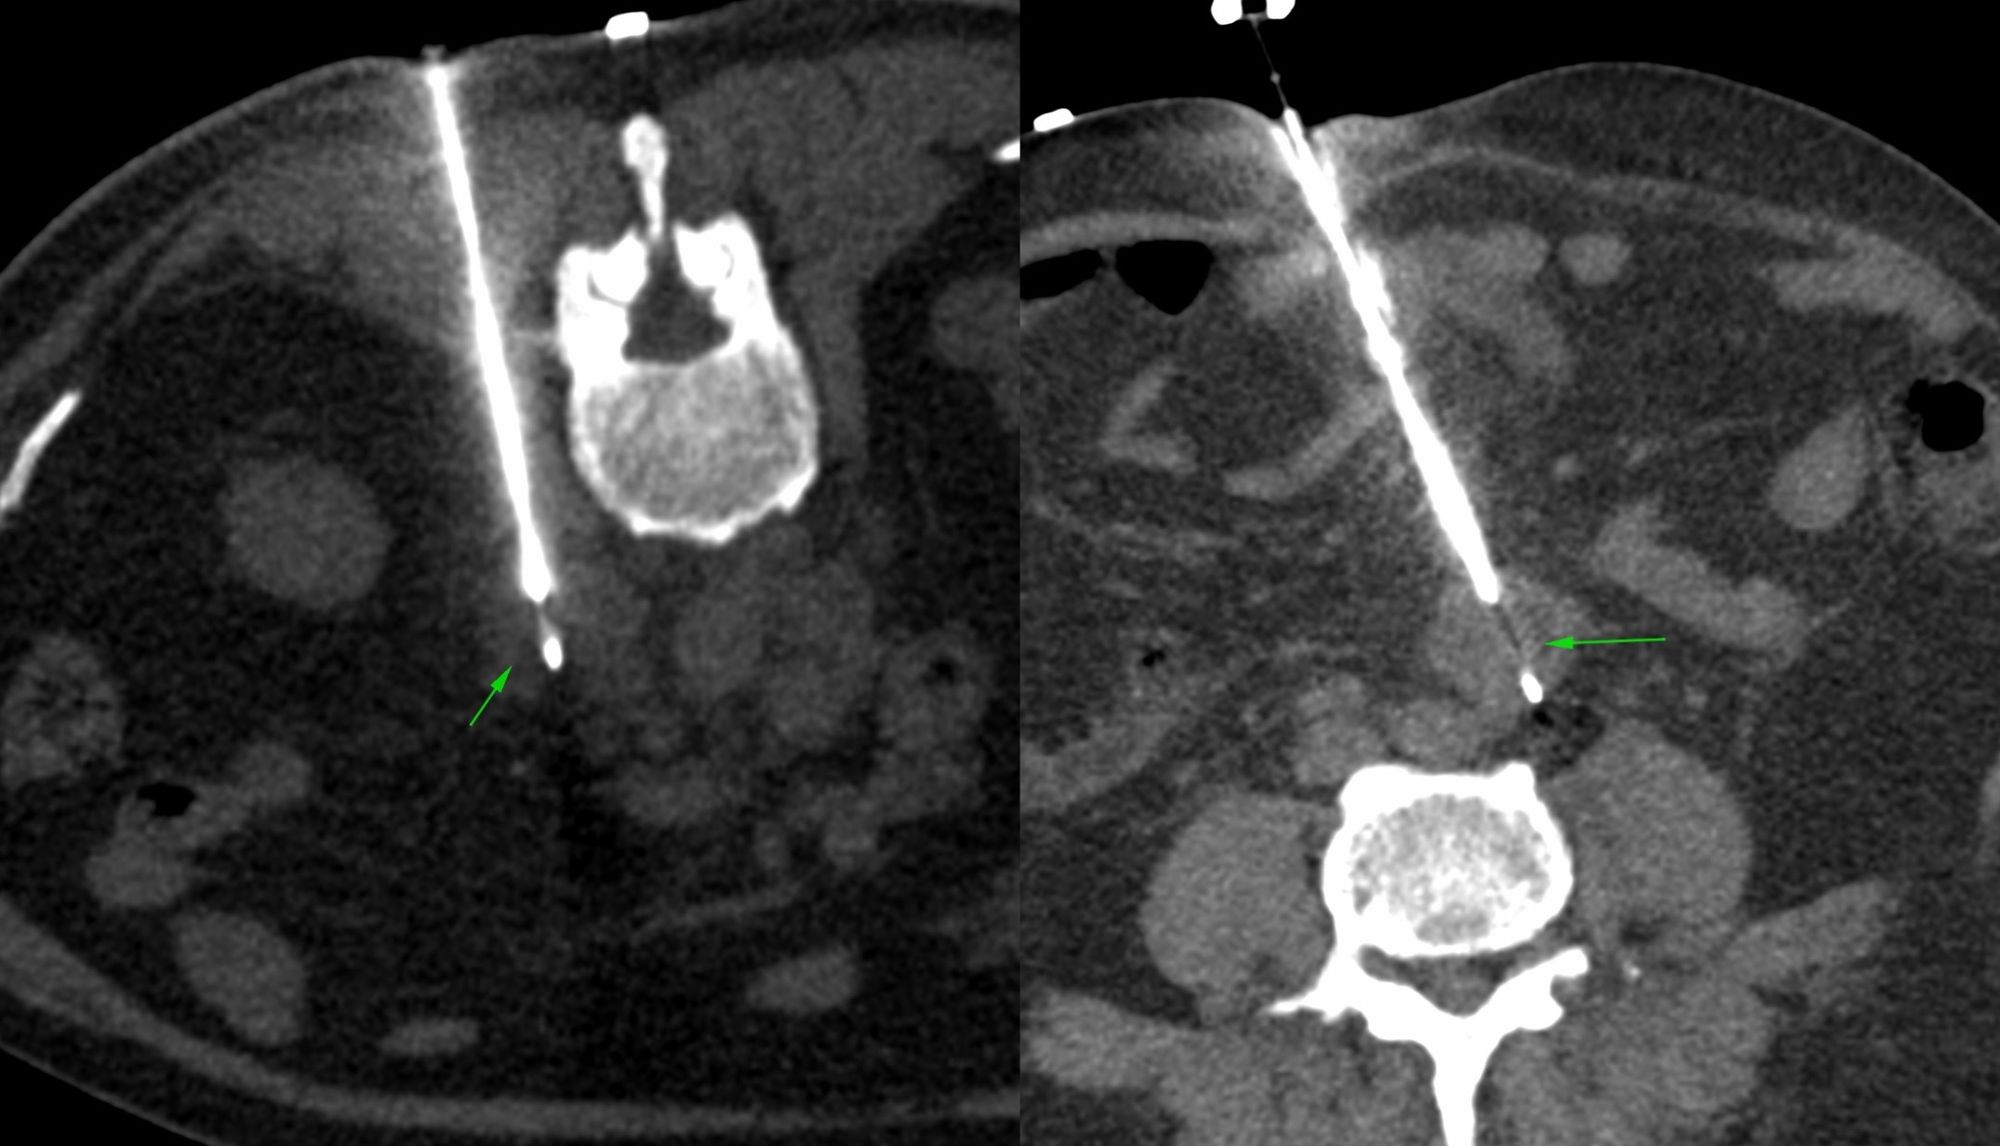

Case 43: Retroperitoneal Node Biopsy - First Prone, Then Supine

Case 42: Complex Retroperitoneal Mass with Intra-Procedural Intravenous Contrast